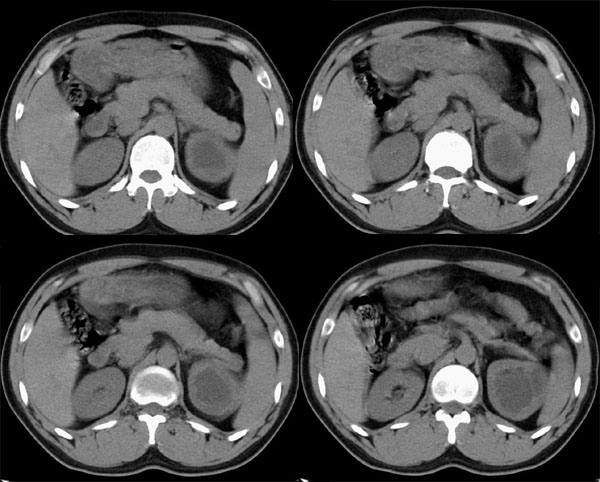

m29y平常体健,无明显不适。单位体检时发现左肾区病变。来我院作ct如下(病人不做增强):

左侧输尿管冠、矢状重建: